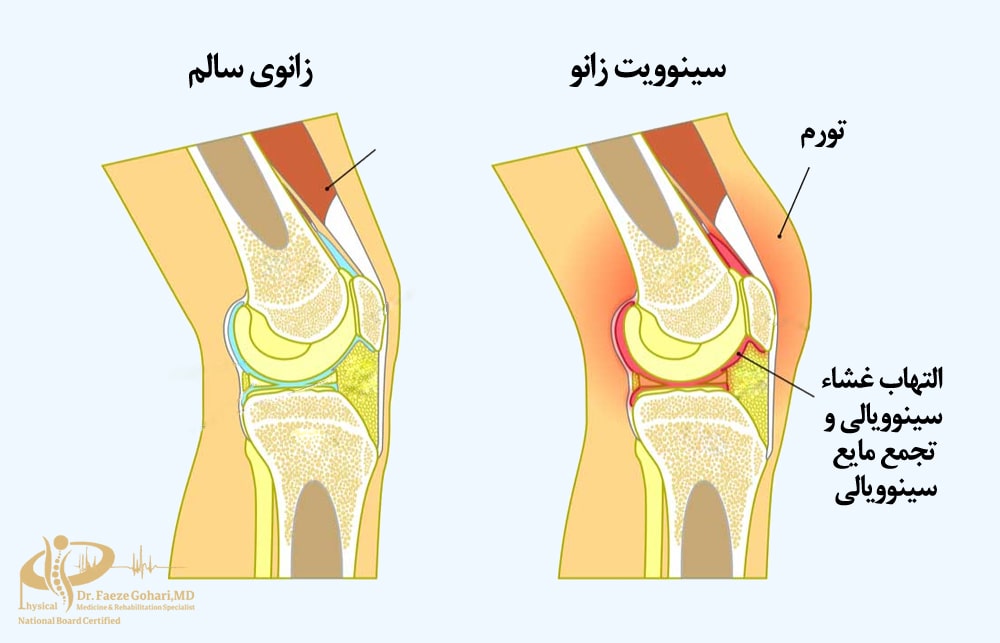

التهاب سینوویال یا بورسیت زانو

پیآرپی میتواند در درمان التهابهای مزمن و غیرعفونی مفصل زانو – مانند بورسیت ناشی از فشار مکانیکی یا استفادة بیش از حد – مؤثر باشد. بااینحال، در مواردی که عفونت فعال وجود دارد (مانند آرتریت یا بورسیت عفونی)، استفاده از این روش توصیه نمیشود، زیرا ممکن است التهاب را تشدید کند. بهطورکلی اثربخشی PRP به شدت التهاب و علت زمینهای بستگی دارد و تشخیص مناسببودن این درمان بر عهدة پزشک متخصص است.

کشیدن مایع مفصلی (در صورت لزوم)

اگر مفصل زانو دچار تجمع غیرعادی مایع شده باشد (مثلاً در موارد التهاب یا تورم)، قبل از تزریق PRP ممکن است مقداری از این مایع با سرنگ تخلیه شود تا فضا برای تزریق فراهم شود و اثر درمانی بهبود یابد.